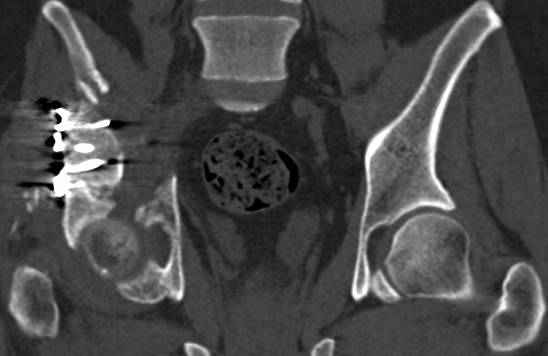

высылаю дополнительно сканы.

Судя по представленным реконструкциям (не очень хорошего качества - много наводок)

мы имеем дело с полупоперечным переломом у которого отломался задний край или его отломали, превратив перелом в полный двухколонный.

По отдельным срезам и тем более по реконструкции трудно судить о сращении крыла и задней колонны с осевым скелетом.

В большинстве случаев при двухколонных переломах

в итоге получается прочный бублик с дыркой. При эндопротезировании в дырку помещается головка, а чашка должна неплохо заклиниться в бублике.

Главное, чтобы бублик не был разорван, что не очень понятно на представленных снимках.

Все выступающие коллеги высказались насчет необходимости стандартных снимков по Judet, потому что для определения тактики лечения переломов вертлужной впадины 3Д снимки малоинформативны.

Из того минимума, что представлено, мне кажется, мы имеем дело с двухколонным переломом вертлужной впадины. Обычно медиальный (центральный) "вывих" головки встречаются в сложных двухколонных переломах со смещением.